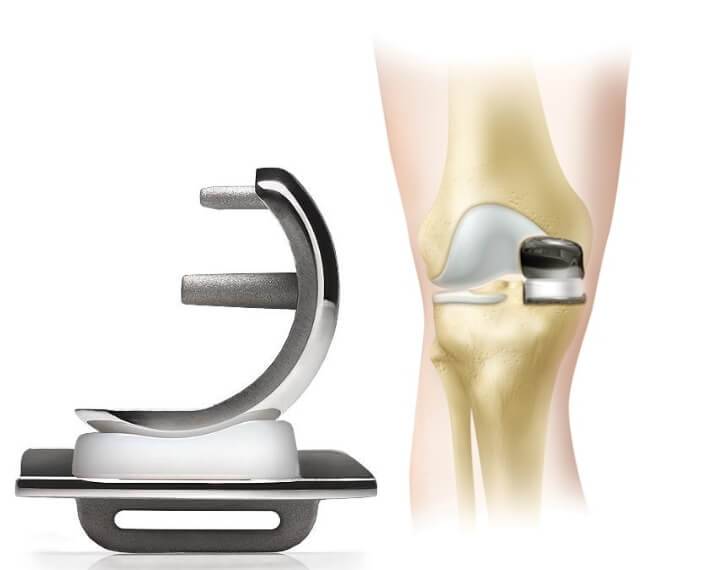

Примеры протезов коленных суставов Zimmer